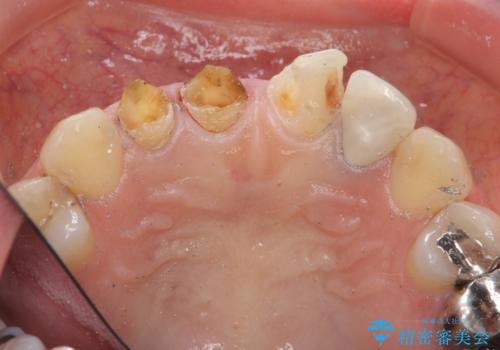

- 前歯を天然の歯のようにきれいにやりかえたいと希望され来院されました。

根尖病変の存在が判明したため、感染根管治療後にオールセラミックジルコニアクラウンを製作します。